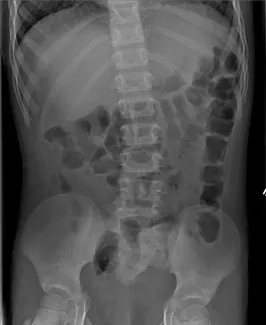

Abdominal Xrays are necessary to evaluate the effectiveness of the laxative or enema therapy and to identify the amount of stool in the colon. These will be done at each office visit.

Also, the surgeon or surgical nurse will determine if there is hard stool by rectal exam. If found, this can be treated by enemas or suppositories, If these fail to help the stool pass, it might be necessary to disimpact the stool in the operating room, under anesthesia.

Firm bowel movements can be painful to pass. This can lead to stool with-holding which further worsens constipation. Blood streaks lining the firm stools may mean anal fissures, which are cracks or tears near the anus caused by passing hard stools. If this is noted, increase fluid intake and call our office to schedule a clinic visit and an abdominal Xray. The dose of oral laxatives may need be increased before the clinic visit.